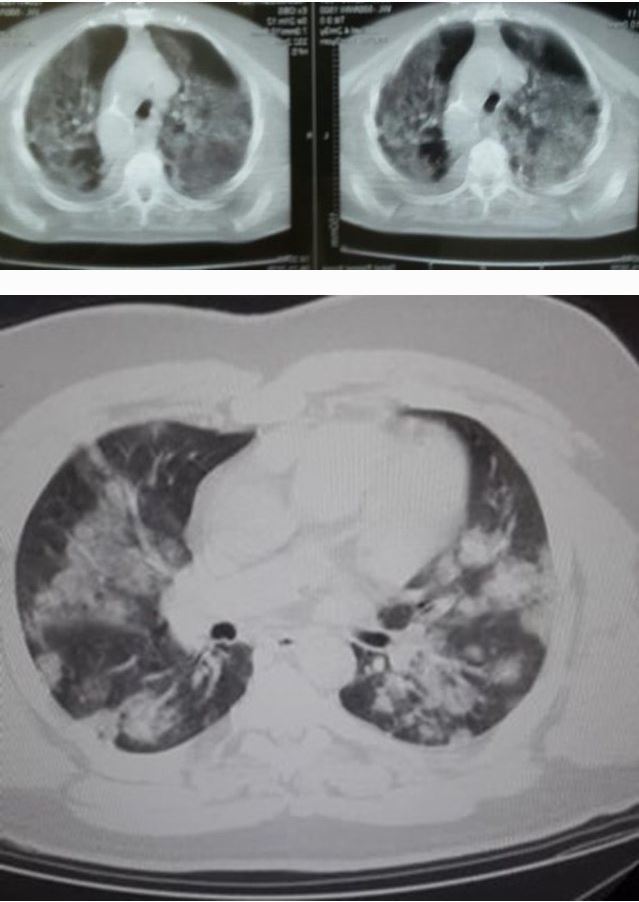

FOTOT: Po prek të rinjtë, Kalo nxjerr pamjet alarmuese: Bëni kujdes vëllezër e motra pa dallim feje, krahine e ideje